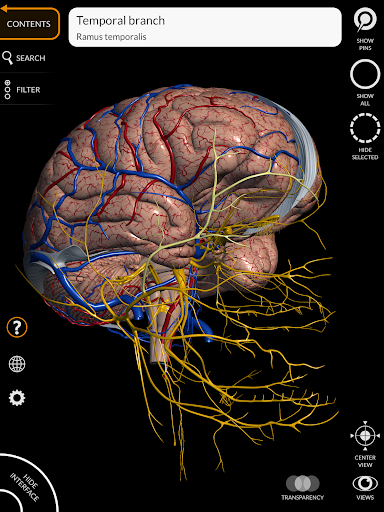

يتيح لك "Anatomy 3D Atlas" دراسة التشريح البشري بطريقة سهلة وتفاعلية.

من خلال واجهة بسيطة وبديهية، من الممكن ملاحظة كل بنية تشريحية من أي زاوية.

تتميز النماذج التشريحية ثلاثية الأبعاد بتفاصيل خاصة ودقة تصل إلى 4K.

• الجهاز العصبي

• من خلال تحديد نموذج أو دبوس، يظهر المصطلح التشريحي ذي الصلة

• وصف العضلات: الأصل والإدخال والتعصيب والعمل

• المصطلحات التشريحية وواجهة المستخدم متوفرة بـ 11 لغة: اللاتينية والإنجليزية والفرنسية والألمانية والإيطالية والبرتغالية والتركية والروسية والإسبانية والصينية واليابانية والكورية

• يمكن عرض المصطلحات التشريحية بلغتين في وقت واحد